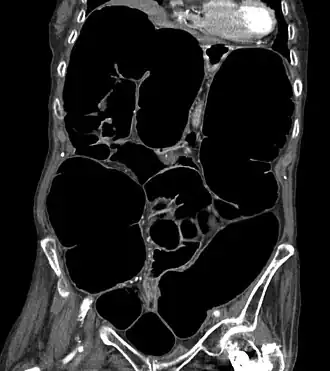

![]() Tomografía computarizada que muestra una sección coronal del abdomen de una anciana con síndrome de Ogilvie | ||